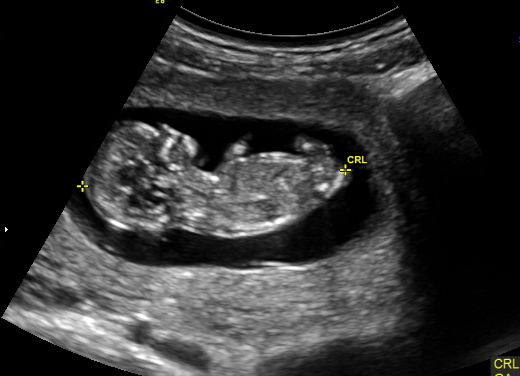

I am currently 15 weeks and have an ultrasound in 4 weeks to find out gender. The pictures below are at 12 weeks. I have 3 awesome boys and would love a girl for my final babe. Thoughts? Thanks so much!Attachment 11991Attachment 11990

Sorry I cannot see a nub but the skull looks girly. Fingers crossed for you.

Sorry I can't see any gender clues but I hope it's your pink one x

Can't make out pink or blue from these sorry xx